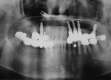

Purpose: To report the clinical and radiological characteristics of a patient who experienced dental implant displacement into the maxillary sinus following sinus floor elevation, and to compare our findings with those of other published reports of the displacement of dental implants.

Materials and methods: Implant placement and maxillary sinus elevation were performed simultaneously. The location of the displaced implant was monitored for 8 years, until the ectopic implant was surgically removed using the lateral window approach. The contributing factors, treatment modality, and clinical outcome for our patient were compared with those of patients reported in the literature.